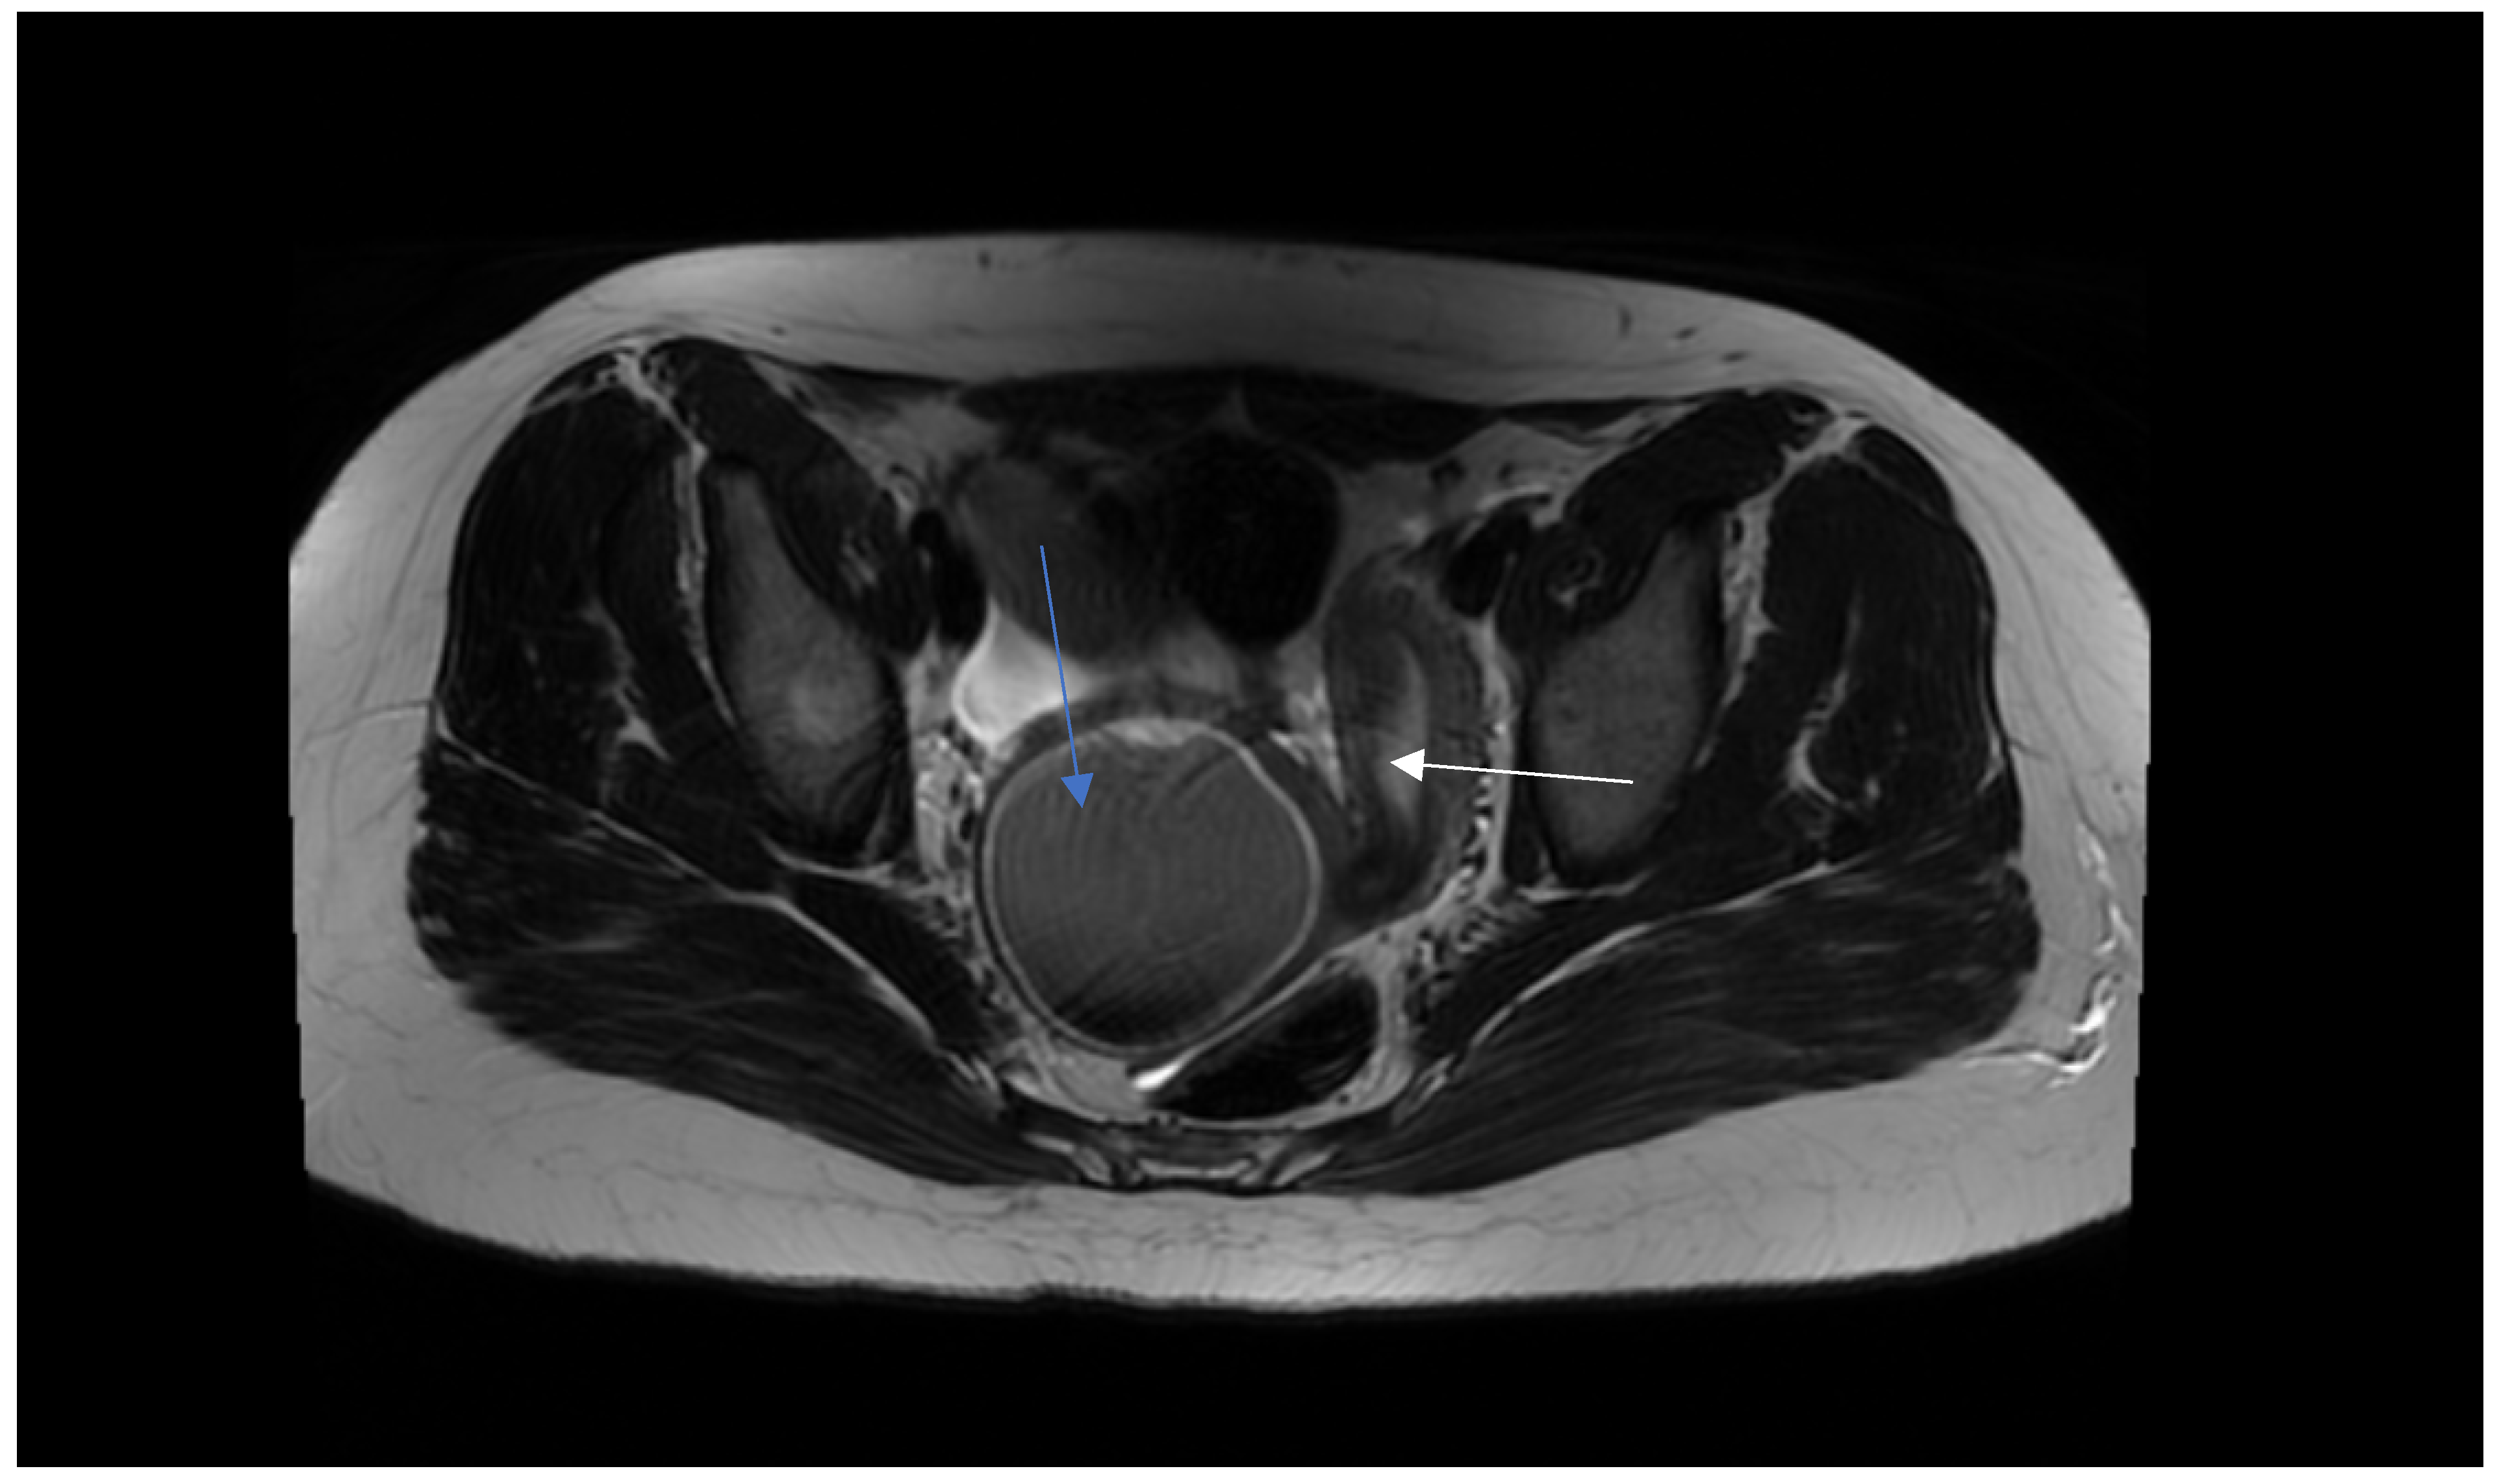

2.2. Preoperative Management